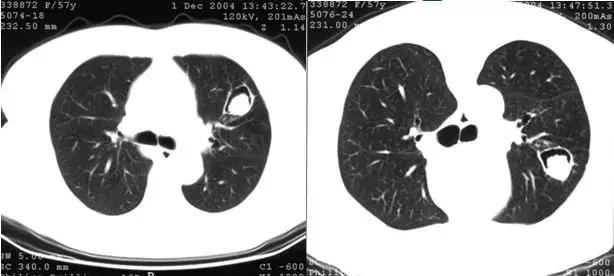

肺内空洞或空腔内的球形病灶与洞壁之间形成的新月形透亮影称为“空气新月征”。

空气新月征曾认为是曲霉菌球的特异征象,特点是随着体位的变动,空洞或空腔内的霉菌球可移动,但始终位于近地位。也可见于其他疾病(其内球形病灶可能不移动)

仰卧与俯卧位CT扫描,霉菌球始终处于近地位,空气新月征位于上方

“空气新月征”也可见于肺结核病例,常伴有钙化,多不随体位而变动